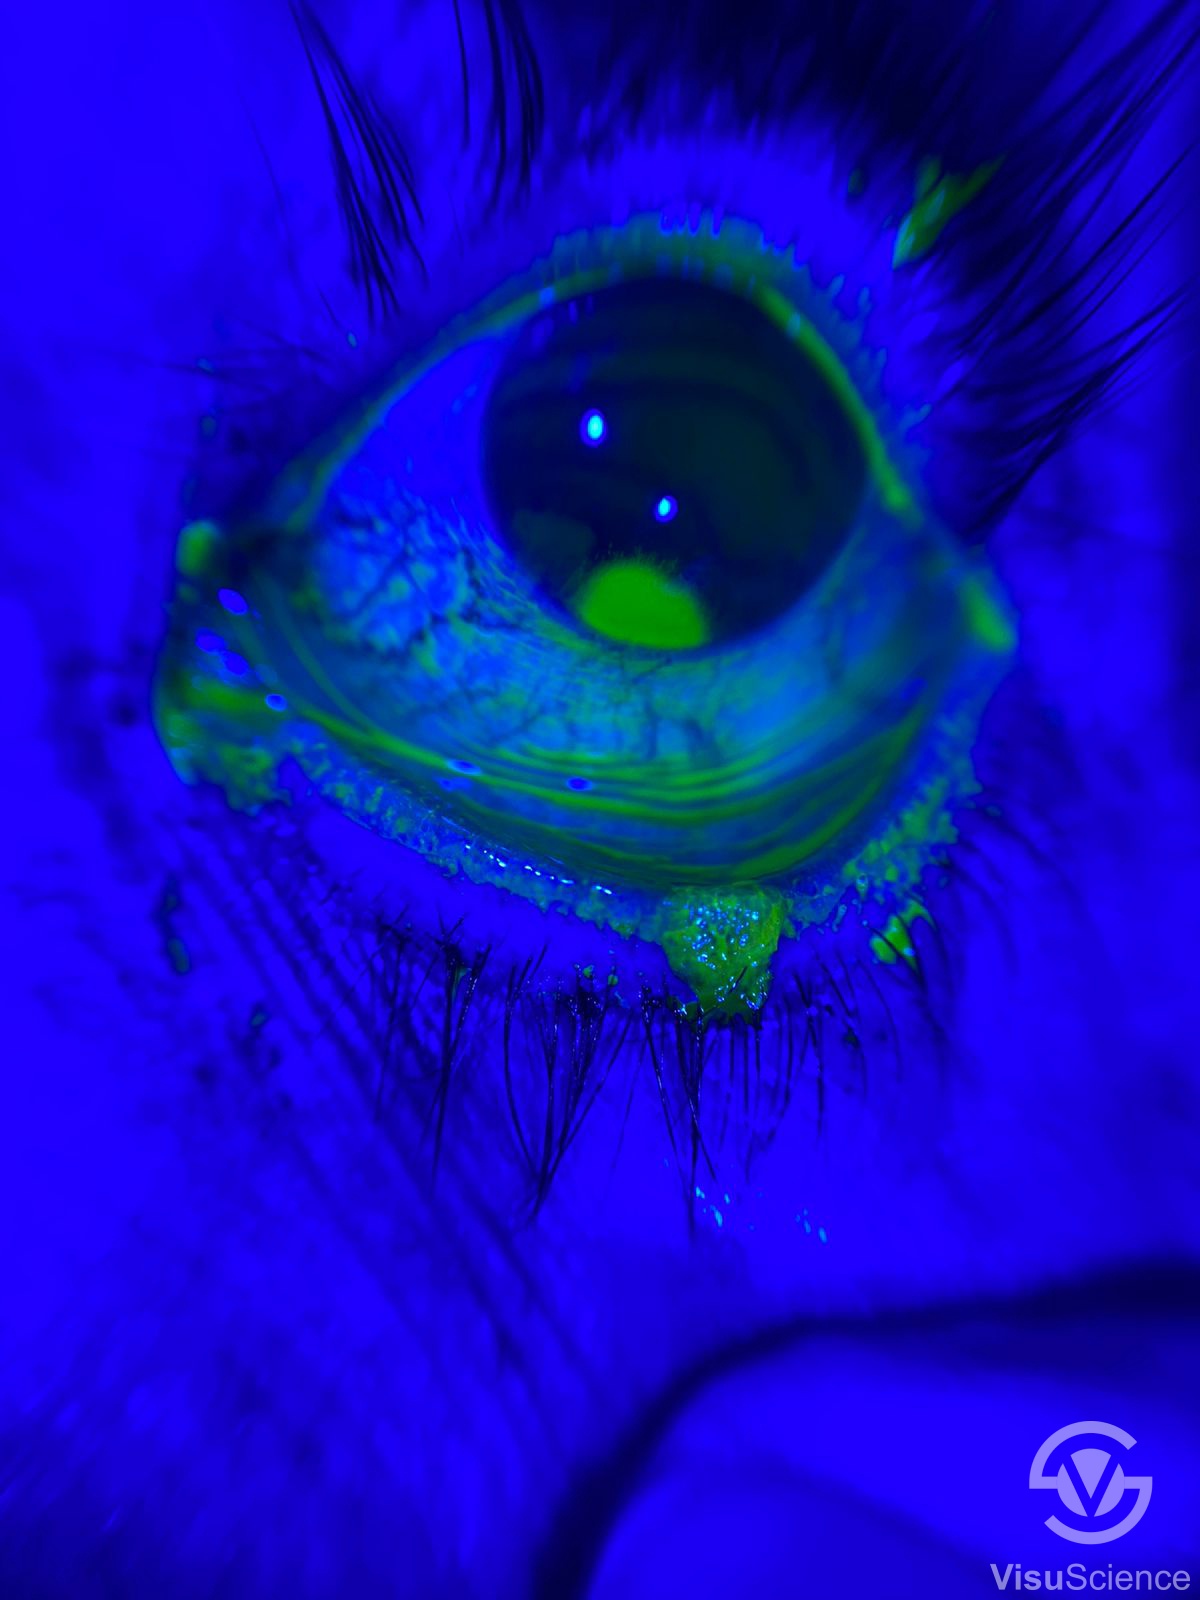

Weiße und blaue Beleuchtung

QuikVueTM bietet sowohl weiße als auch blaue Beleuchtung. Die weiße LED projiziert warmweißes Licht, das der Halogenbeleuchtung einer Spaltlampe ähnelt. Es stehen zwei Weißbeleuchtungsstufen zur Verfügung, um den unterschiedlichen Helligkeitsanforderungen während der Untersuchung gerecht zu werden. Die blaue Beleuchtung kann verwendet werden, um Fluoreszeinbilder aufzunehmen, um die Diagnose bei Hornhautfärbung und Kontaktlinsenanpassung usw. zu unterstützen.

Pathologische Bilder, aufgenommen von Dr. Hesham Mahmoud Eissa

Kontaktlinsenbedingte Hornhautinfektion vor empirischer

Behandlung mit angereicherten Augentropfen, achten

Sie auf die Größe des grün gefärbten Geschwürs

Derselbe Fall zeigte nach einer Behandlungswoche eine

Abnahme der Geschwürgröße

Gleicher Fall nach einer Woche Behandlungsfoto mit Blaufilter